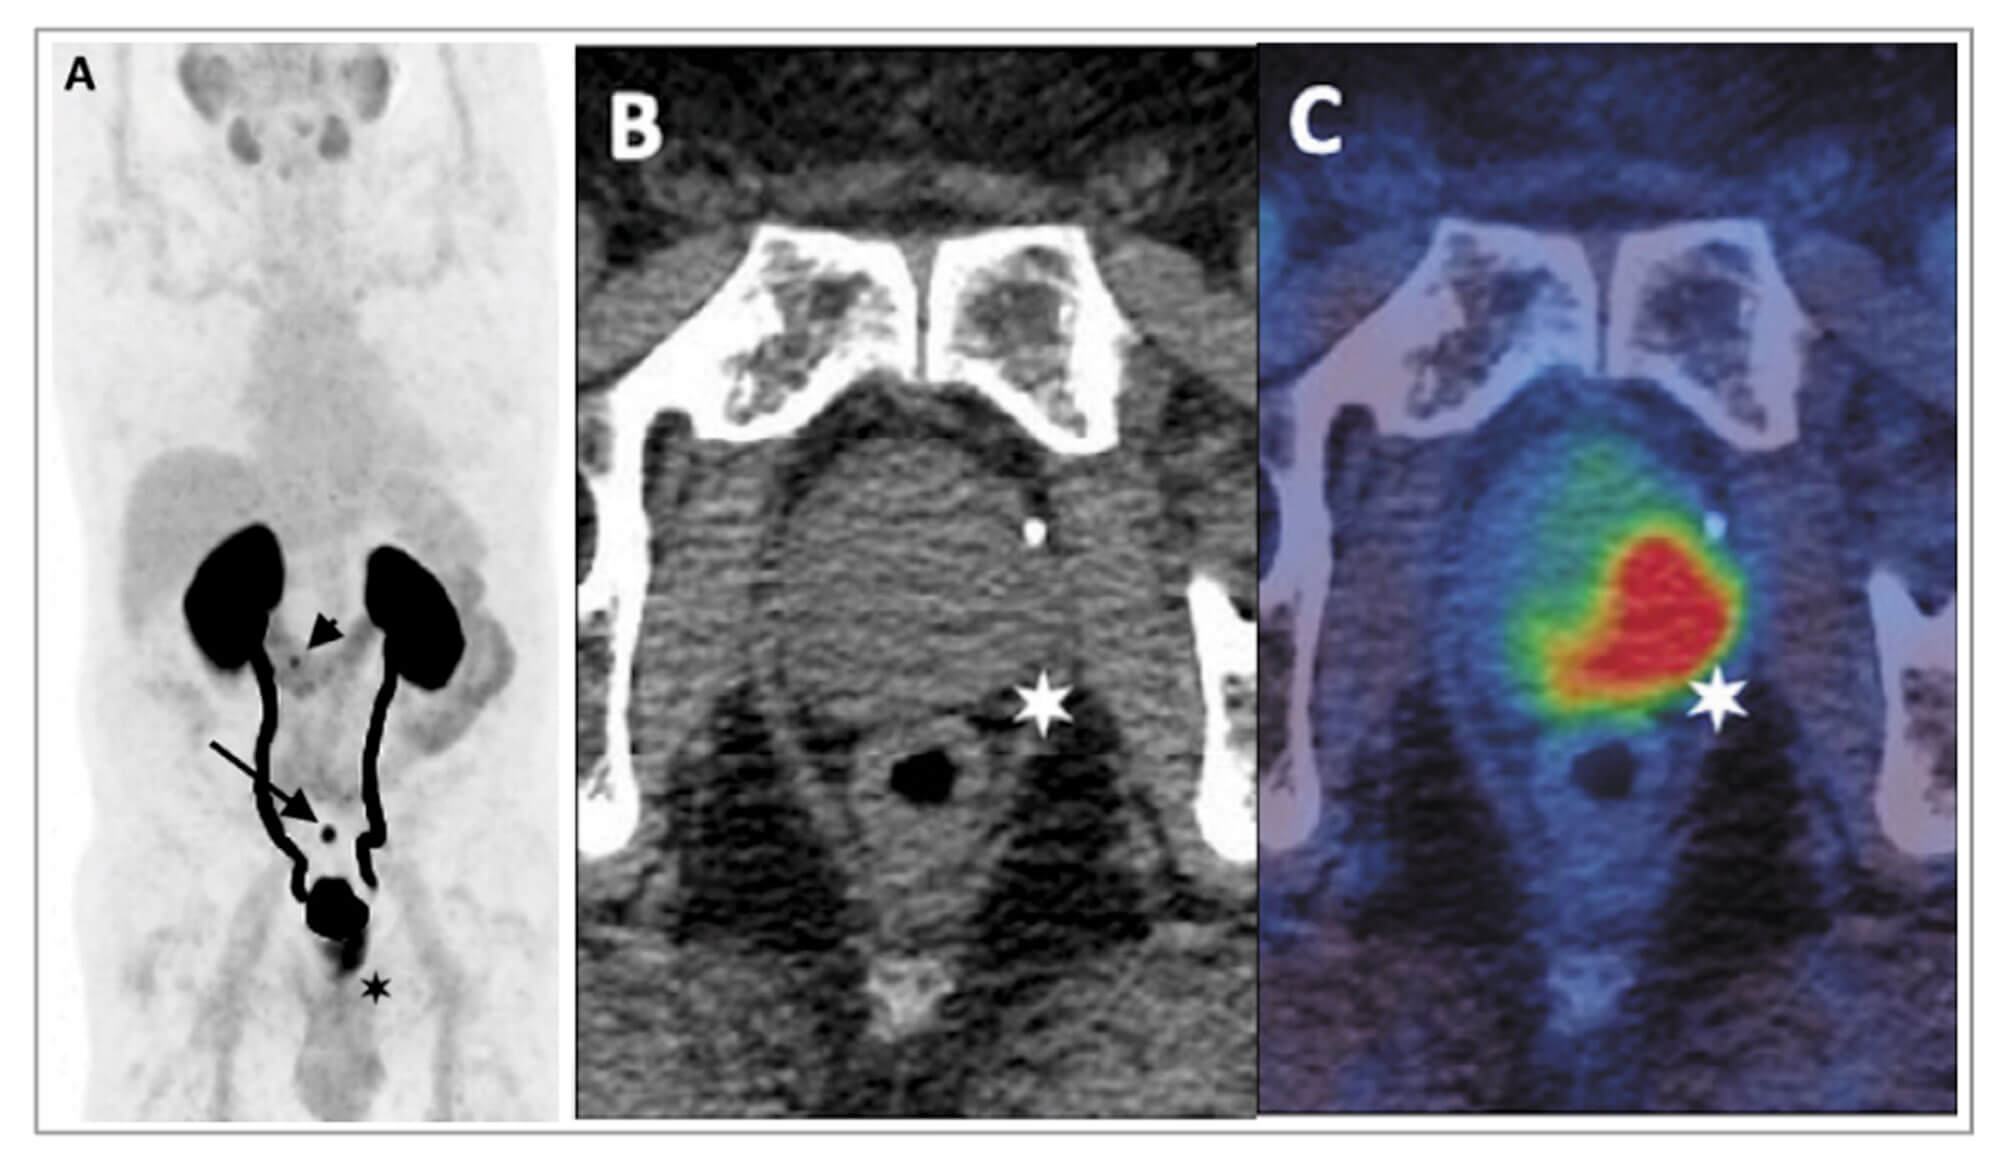

Figure 2: 68Ga-THP-PSMA PET-CT in staging of primary prostate cancer.

A: PET image B: Axial CT C: Fused PET-CT image

Images demonstrate high-grade uptake in a predominantly left-sided prostatic tumour

with low-grade uptake in a 6mm left internal iliac node (arrow on PET, star on fused images).

There are an increasing number of studies demonstrating the superiority of 68Ga- labelled PSMA PET-CT over conventional imaging for CaP staging (Figure 2). A prospective study of 113 patients confirmed significantly higher sensitivity (96.2% vs. 73.1%) and accuracy (99.1 vs. 84.1%) using 68Ga-labelled PSMA PET-CT compared with BS for metastatic bone disease [8].

Several studies have assessed the diagnostic performance of 68Ga-labelled PSMA PET-CT for nodal staging with histopathological validation. The largest series of 208 patients reported a sensitivity for nodal disease of 38.2% (21 of 55 patients) and a per node sensitivity of 24.4% (42 of 172 nodes). The median diameter of a malignant node was 4.8mm, with 15% of histologically-proven malignant nodes measuring <5mm [9].

The ProPSMA study, an Australian, multicentre, prospective, randomised controlled trial, of 300 patients with a primary CaP, compared 68Ga-labelled PSMA PET-CT with conventional imaging [10]. PSMA PET-CT had a 27% greater accuracy compared to conventional imaging (92% vs. 65%). The results of conventional imaging resulted in a treatment change for 23 men compared with 41 men following PSMA PET-CT. Conventional imaging was also associated with a higher radiation dose (19.2mSv compared to 8.4mSv). The group have also reported data on favourable cost outcomes of PSMA PET-CT, further demonstrating the clinical utility of this technique [10].

68Ga-labelled PSMA PET-CT has been shown to have a significant impact on management, with Roach et al. demonstrating a 21% change in management intent and Kulkarni et al. a 24% change respectively [11-12].